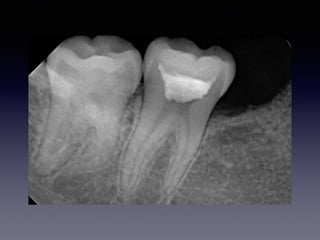

#30 Partial pulpotomy

follow-up case

(23 female)

2013 01 26

2012 10 13

23m later

26

21m later